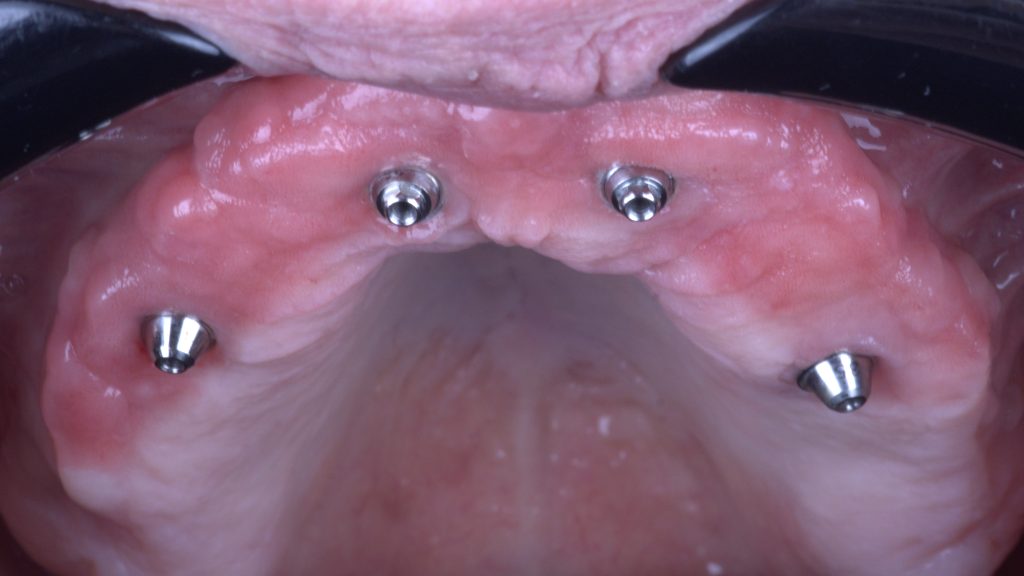

Keratinized tissue

After six months of healing we find healthy keratinized mucosa around implants and restoration

Keratinized peri-implant mucosa

It is a joy to observe perfect soft tissue healing Just look at the robust band of keratinized gingiva